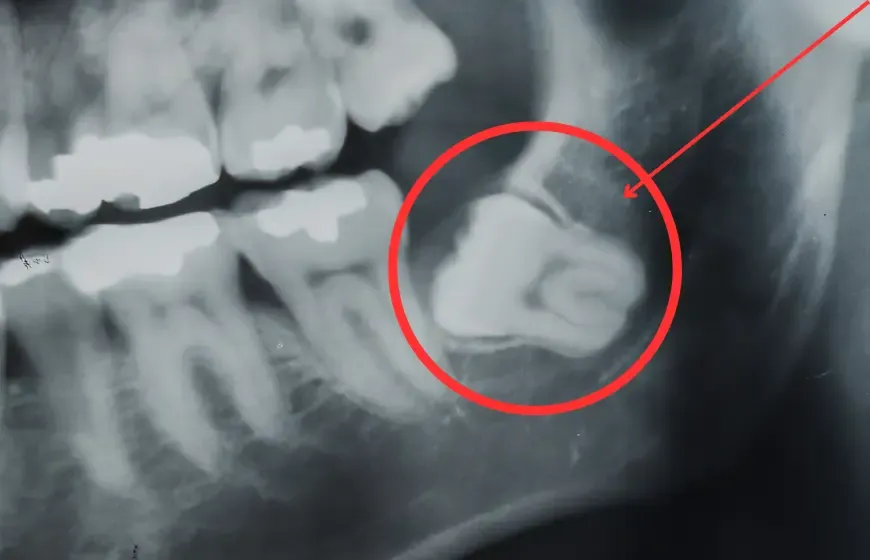

Zęby mądrości, czyli ósemki, zazwyczaj pojawiają się w jamie ustnej między 17. a 25. rokiem życia. Problem w tym, że współczesna szczęka człowieka, w wyniku ewolucji i zmian w diecie, często jest mniejsza niż u naszych przodków. W efekcie, dla wszystkich czterech ósemek nierzadko brakuje miejsca w łuku zębowym, co prowadzi do ich zatrzymania lub nieprawidłowego wyrzynania się.

Nie u każdego ósemki się wyrzynają lub wyrzynają się tylko częściowo. Typowy przedział wiekowy ich pojawiania się to wspomniane wcześniej 17-25 lat, ale zdarza się, że pojawiają się później lub wcale. Brak miejsca może powodować, że ząb pozostaje całkowicie zatrzymany w kości szczęki lub żuchwy.

Typowe problemy związane z zatrzymanymi ósemkami to między innymi ból, stany zapalne dziąseł, ucisk na sąsiednie zęby, a nawet powstawanie torbieli. Z tych powodów, często pojawiają się ogólne wskazania do ich usunięcia, zwłaszcza jeśli powodują dyskomfort lub stanowią potencjalne zagrożenie dla zdrowia pozostałych zębów.